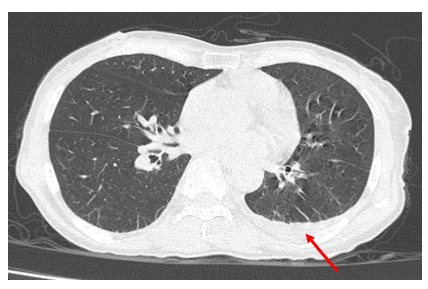

Chụp CT lồng ngực:

Hình 4: Hình ảnh vài dải xẹp phổi thùy dưới phổi hai bên. Ít dịch màng phổi trái

10 mm (mũi tên đỏ).